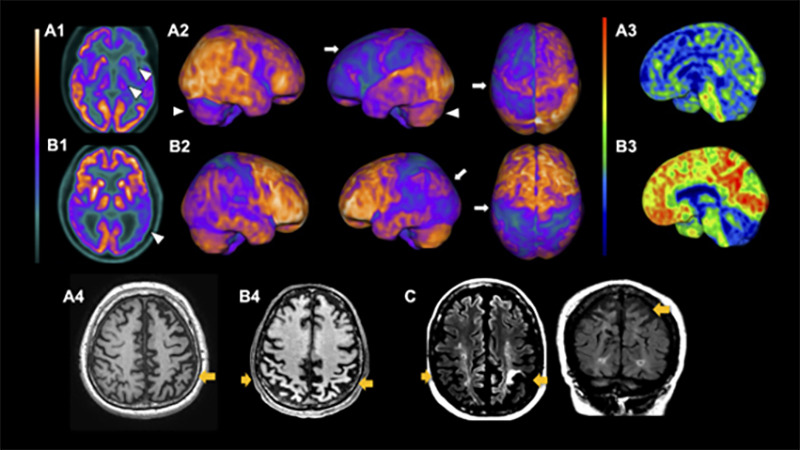

In PSP, the imaging hallmark is midbrain atrophy, which can be assessed through the visual identification of the “hummingbird sign”ref. B45 (specificity 99%, sensitivity 50%) on the sagittal plane, the “morning glory flower sign”ref. B46 (specificity 97%, sensitivity 37%) on the axial plane, and the superior cerebellar peduncle atrophy in the coronal plane (Figure 2)ref. B47 , ref. B48. More objective measures that can help diagnose PSP include the area, diameter, and volume of the midbrainref. B49, pons-midbrain area ratioref. B50, and the parkinsonism index MRPI (magnetic resonance parkinsonism index), calculated through the measurement of the ratios of the pons to midbrain area and middle cerebellar peduncle to superior cerebellar peduncle widthsref. B50. The latter is especially sensitive and specific for distinguishing PSP from PD, multiple system atrophy-parkinsonian type (MSA-P), and healthy controlsref. B51. Apparent diffusion coefficient (ADC) increased values in the putamen and superior cerebellar peduncle have good sensitivity and specificity in differentiating PSP-RS from PDref. B52. Also, diffusion tensor imaging (DTI) may show a degeneration pattern suggestive of PSP-RSref. B53.

Although these MRI findings are valuable for differentiating PSP-RS from other parkinsonian syndromes with high specificity, they are less sensitive than PSP clinical diagnosis in its distinction from other degenerative parkinsonismsref. B46 , ref. B49. Another limitation is that most studies restricted their subjects to patients presenting with a PSP-RS phenotype. One of the few studies that included PSP presentations other than RS showed that cortical variants (PSP-CBS, PSP-F, PSP-SL) had more frontal atrophy than subcortical variants (PSP-RS, PSP-P, PSP-PGF)ref. B54.

CBD, in its turn, usually presents supratentorial patterns of atrophy, mainly asymmetrical patterns in the posterior frontal, superior parietal lobe, and basal ganglia (Figure 3). Cortical thinning and subcortical volume loss prominently involve the hemisphere contralateral to the more affected limb. Also, motor severity negatively correlates with the contralateral cortical thinning in the precentral and postcentral gyri and with volumes of putamenref. B59. Moreover, multimodal MRI studies search for CBS patterns of structural lesions that may suggest underlying pathology. A clinicopathologic study suggested that patterns of gray matter loss in CBS differ according to the underlying pathologyref. B60. Individuals with CBS and a postmortem diagnosis of CBD and PSP displayed similar focal atrophy at premotor and supplementary motor areas. In contrast, patients with underlying FTD-TDP43 and AD pathology had a more widespread pattern of gray matter loss at the frontotemporal lobe and temporoparietal regions, respectivellyref. B60.

The brain metabolic patterns obtained from FDG-PET assist in the early diagnoses of neurodegenerative diseases and is helpful to differentiate Parkinson’s disease from atypical parkinsonismref. B61 , ref. B62. FDG-PET in PSP-RS shows a characteristic pattern of hypometabolism in the midbrain, basal ganglia, thalamus, and frontal lobes, including prefrontal, anterior cingulate, premotor, and motor regionsref. B61 , ref. B63. A typical asymmetrical hypometabolism in CBD involves the frontal and parietal lobes, basal ganglia, and thalamus (Figure 2).

Although CBD displays a characteristic frontoparietal asymmetric hypometabolismref. B64, CBS shows a more complex set of metabolic patterns due to its diverse neuropathologies. A recent study with neuropathologic examination showed that CBS underlying pathologies are associated with different metabolic degeneration patterns and described hypometabolism for CBS-CBD, CBS-AD, and CBS-PSPref. B65. Another prospective study using FDG-PET and amyloid-PET in a CBS cohort showed that individual brain metabolic patterns could distinguish with high specificity and accuracy CBS due to AD pathology from CBS non-AD pathological variantsref. B66, suggesting that it might be routinely used in the clinical workup of CBS. Accordingly, CBS-AD shows distinct metabolic signatures, such as a more posterior temporoparietal pattern and less frontal hypometabolism, compared to CBS not related to AD pathologyref. B65 , ref. B66. As neurodegeneration modulates metabolism, the metabolism also can depict its clinical features and clinical variants in CBSref. B66 , ref. B67.

Concerning PSP, however, there is still uncertainty regarding its usefulness in distinguishing PSP clinical variants. A previous study demonstrated that FDG-PET is a reproducible diagnostic tool for PSP-RS and PSP-P variantsref. B68.

Moreover, PET tracers that bind to the protein tau aggregated as neurofibrillary tangles have been developed and performed in PSP and CBD patients. Prior studies using the first generation of tau-targeting tracers, the most widely used ref. B18F-AV-1451 (also known as flortaucipir), showed good correspondence between in vivo imaging and postmortem PSP and CBD evaluationref. B54 , ref. B69 , ref. B70. Also, it was helpful to distinguish between CBS, PSP, and ADref. B69, and the uptake in globus pallidus might be a valuable measure for differentiating PSP-RS from PDref. B70. Nevertheless, as the ultrastructural characteristics of tau filaments differ across diseases, first-generation tau tracers demonstrate more affinity to paired helical filaments found in AD (tau 3R/4R) than straight filaments found in 4R-tauopathiesref. B10.

In contrast, second-generation tau PET tracers such as [18F]PI-2620 demonstrated more specificity for 4R-tauopathies. Elevated uptake has been observed in several areas in PSP-RS, such as globus pallidus, subthalamic nucleus, putamen, substantia nigra, and dentateref. B71. The same tracer has been studied in CBS and demonstrated to help diagnose underlying pathology and potentially monitor disease progressionref. B72.